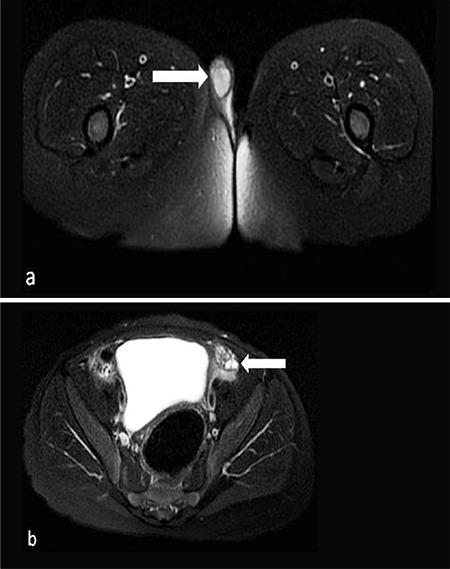

The 46,XX ovotesticular disorder of sex development (DSD) is rarely observed in humans. This disorder is generally described as ambiguous genitalia with the presence of ovarian and testicular tissues in different gonads or in the same gonad. Almost no subjects with 46,XX ovotesticular DSD have sex-determining region of the Y chromosome (SRY) gene. It is known that excessive expression of SRY-related high mobility group box 9 (SOX9) is the cause of SRY-negative 46,XX ovotesticular DSD in the absence of SRY. Here, we analyzed our SRY-negative case with 46,XX ovotesticular DSD. In an array comparative genomic hybridization study using a peripheral blood sample from the patient, a duplication of 1114 kb (Hg19 coordinates: chr17:69006280-70120619) in the region of 17q24.3 containing SOX9 was detected. This is the first case reported from Turkey, exhibiting SOX9 duplication in SRY-negative 46,XX ovotesticular DSD.

46,XX 卵睾性性发育障碍(DSD)在人类中很少见。这种疾病通常表现为生殖器模糊,在不同的性腺或同一性腺中存在卵巢和睾丸组织。几乎没有 46,XX 卵睾性 DSD 患者存在 Y 染色体性别决定区(SRY)基因。已知 SRY 相关高迁移率族蛋白 9(SOX9)的过度表达是在没有 SRY 的情况下导致 SRY 阴性 46,XX 卵睾性 DSD 的原因。在这里,我们分析了我们的 SRY 阴性 46,XX 卵睾性 DSD 病例。在使用来自患者外周血样本的阵列比较基因组杂交研究中,在包含 SOX9 的 17q24.3 区域中检测到 1114 kb 的重复(Hg19 坐标:chr17:69006280-70120619)。这是首例来自土耳其的病例,表现为 SRY 阴性 46,XX 卵睾性 DSD 中的 SOX9 重复。